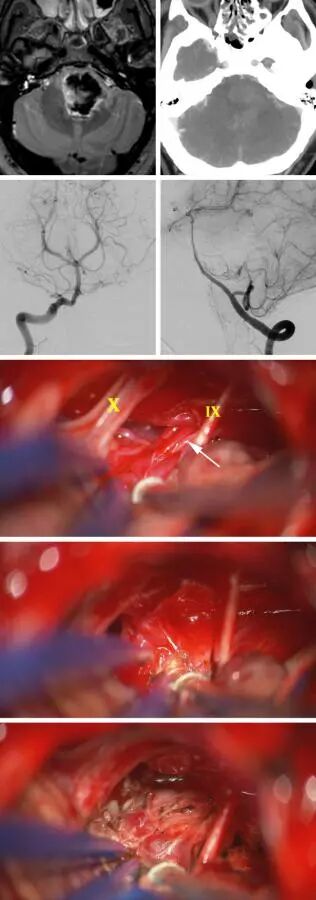

图12:这名不幸的31岁男性表现为突发性偏瘫,检查发现一个巨大的桥脑血肿;CT血管成像相对不明显(上排)。椎动脉造影的前后位与侧位显示一个小型的桥脑延髓AVM,由基底动脉近端与AICA部分供血(第二排)。经左侧乙状窦后开颅显露AVM(第三排)。用原位阻断技术离断畸形巢的血供(第四排)。脑干表面剩余的深色引流静脉也在手术末期进行电凝(末排)。

注:Ⅹ:迷走神经。Ⅸ:舌咽神经。